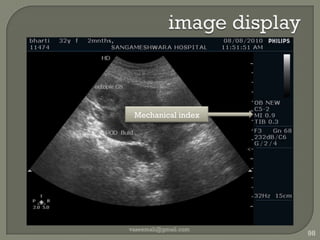

image displayvaseemali@gmail.com55Profile / Preset